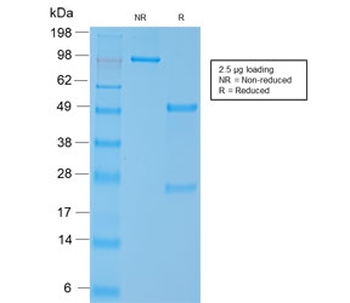

| Catalog Number | orb2638974 |

|---|---|

| Category | Antibodies |

| Description | Smooth muscle myosin heavy chain (SM-MHC) is a cytoplasmic structural protein, which is a major component of the contractile apparatus in smooth muscle cells. Expression of smooth muscle myosin is developmentally regulated, appearing early in smooth muscle development, and is specific for smooth muscle development. Two isoforms of smooth muscle myosin heavy chain have been identified, designated MHC-1 and MHC-2. The antibody may be useful for the study of breast tumors as the presence of an intact layer of myoepithelial cells is an important feature, which may distinguish benign breast lesions and carcinoma in situ from invasive tumors. |

| Species/Host | Mouse |

| Clonality | Monoclonal |

| Clone Number | MYH11/923 |

| Tested applications | IHC-P |

| Reactivity | Human |

| Isotype | Mouse IgG1, kappa |

| Immunogen | Recombinant human protein was used as the immunogen for the SMMHC antibody. |

| Antibody Type | Primary Antibody |

| Dilution range | Immunohistochemistry (FFPE): 1-2ug/ml for 30 min at RT |

| Purity | Protein G affinity chromatography |

| Conjugation | Unconjugated |

| Formula | 0.2 mg/ml in 1X PBS with 0.1 mg/ml BSA (US sourced) and 0.05% sodium azide |

| Hazard Information | This SMMHC antibody is available for research use only. |

| UniProt ID | P35749 |

| Storage | Maintain refrigerated at 2-8°C for up to 2 weeks. For long term storage store at -20°C in small aliquots to prevent freeze-thaw cycles. |

| Buffer/Preservatives | 0.2 mg/ml in 1X PBS with 0.1 mg/ml rAlbumin (US sourced) and 0.05% sodium azide |

| Note | For research use only |

| Application notes | Optimal dilution of the SM-MHC antibody should be determined by the researcher.1. Staining of formalin/paraffin tissues requires boiling tissue sections in 10mM Citrate buffer, pH 6.0, for 10-20 min followed by cooling at RT for 20 min.2. The prediluted format is supplied in a dropper bottle and is optimized for use in IHC. After epitope retrieval step (if required), drip mAb solution onto the tissue section and incubate at RT for 30 min. |

| Expiration Date | 12 months from date of receipt. |